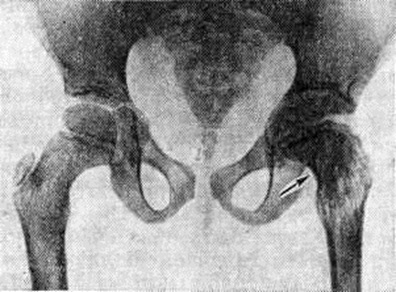

Туберкулёзный Остеоартрит диагностируется на основании регионарного остеопороза, околосуставного очага костной деструкции с неровными нечёткими контурами, сужения суставной щели вследствие разрушения суставных хрящей. В случаях поздней диагностики болезни обнаруживают контактную деструкцию в других костях, образующих сустав (рисунок 1). При туберкулёзном поражении крупного сустава первичный костный очаг на обычных рентгенограммах может не выявляться; его обнаруживают лишь с помощью томографического исследования. Диагностика туберкулёзного Остеоартрит должна подкрепляться характерной клинические, картиной и данными лабораторный исследований.

Рис. 1. | ||